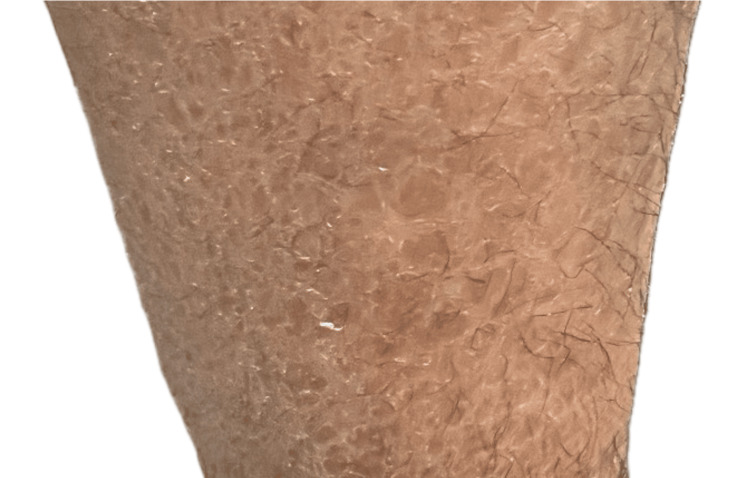

在大學(xué)眼科醫(yī)院進(jìn)行深入檢查后,患者的病史顯示自幼患有慢性濕疹。沒有報(bào)告家族史中有類似皮膚或眼部疾病。盡管經(jīng)過多次治療,他的皮膚干燥、脫屑癥狀持續(xù)存在,主要影響下肢和軀干,屈曲部位受累較輕(圖1)。

圖1:圖1. 下肢出現(xiàn)多邊形、暗色、鱗狀斑塊伴增厚斑塊。

圖1. 下肢出現(xiàn)多邊形、暗色、鱗狀斑塊伴增厚斑塊。

該鱗屑是魚鱗病的特征,盡管經(jīng)過治療,皮膚受累仍然持續(xù)。這些發(fā)現(xiàn)之前被誤診為慢性濕疹。